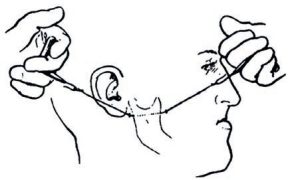

Streszczenie: Agenezja bocznych siekaczy szczęki jest najczęściej występującą anomalią rozwojową zębów. Postępowanie w przypadku braku siekacza bocznego polega na zamknięciu luki z wykorzystaniem kła jako namiastki siekacza albo na ortodontycznym utworzeniu przestrzeni dla uzupełnienia protetycznego. Uważa się, że – ponieważ luka występuje w obszarze estetycznym – odpowiednie podejście do potrzeb pacjenta wymaga starannej diagnostyki i planu leczenia. Taki problem jest dużym wyzwaniem dla ortodontów, protetyków i stomatologów ogólnych. Niniejsze doniesienie kazuistyczne opisuje postępowanie ortodontyczne u 22-letniej dorosłej pacjentki z brakiem górnego lewego bocznego siekacza i widoczną luką w odcinku przednim łuku zębowego, u której dokonano zamknięcia luki za pomocą lateralizacji kła i ukształtowano go w taki sposób, by stanowił namiastkę siekacza. Jednak w celu osiągnięcia optymalnej estetyki i poprawy zgryzu kluczowe są pewne modyfikacje w mechanice leczenia. Zamknięcie luki z wykorzystaniem lateralizacji kła wydaje się mniej inwazyjne, leczenie można zakończyć w stosunkowo krótkim czasie, a kolejny czynnik przemawiający na korzyść tej opcji to adaptacja przemieszczonego zęba do zmian, jakie z biegiem lat zachodzą w obrębie twarzy, bez konieczności uzupełnień protetycznych.